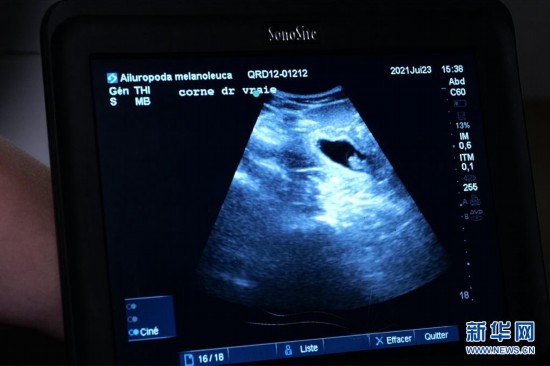

这是7月23日在法国中部圣艾尼昂市博瓦勒野生动物园拍摄的大熊猫“欢欢”的超声波检查照片。新华社发(博瓦勒野生动物园供图)

博瓦勒野生动物园当天发表新闻公报说,继20日发现“欢欢”腹中首个胚胎后,动物园兽医23日在为“欢欢”做超声波检查时,在其子宫另一侧发现第二个胚胎。

博瓦勒野生动物园发言人20日曾宣布,此前对“欢欢”的超声波检查证实其腹中存在胚胎。荷尔蒙分析结果显示,预产期应该在7月底或8月初。兽医团队接下来每周将对“欢欢”进行两次超声波检查。